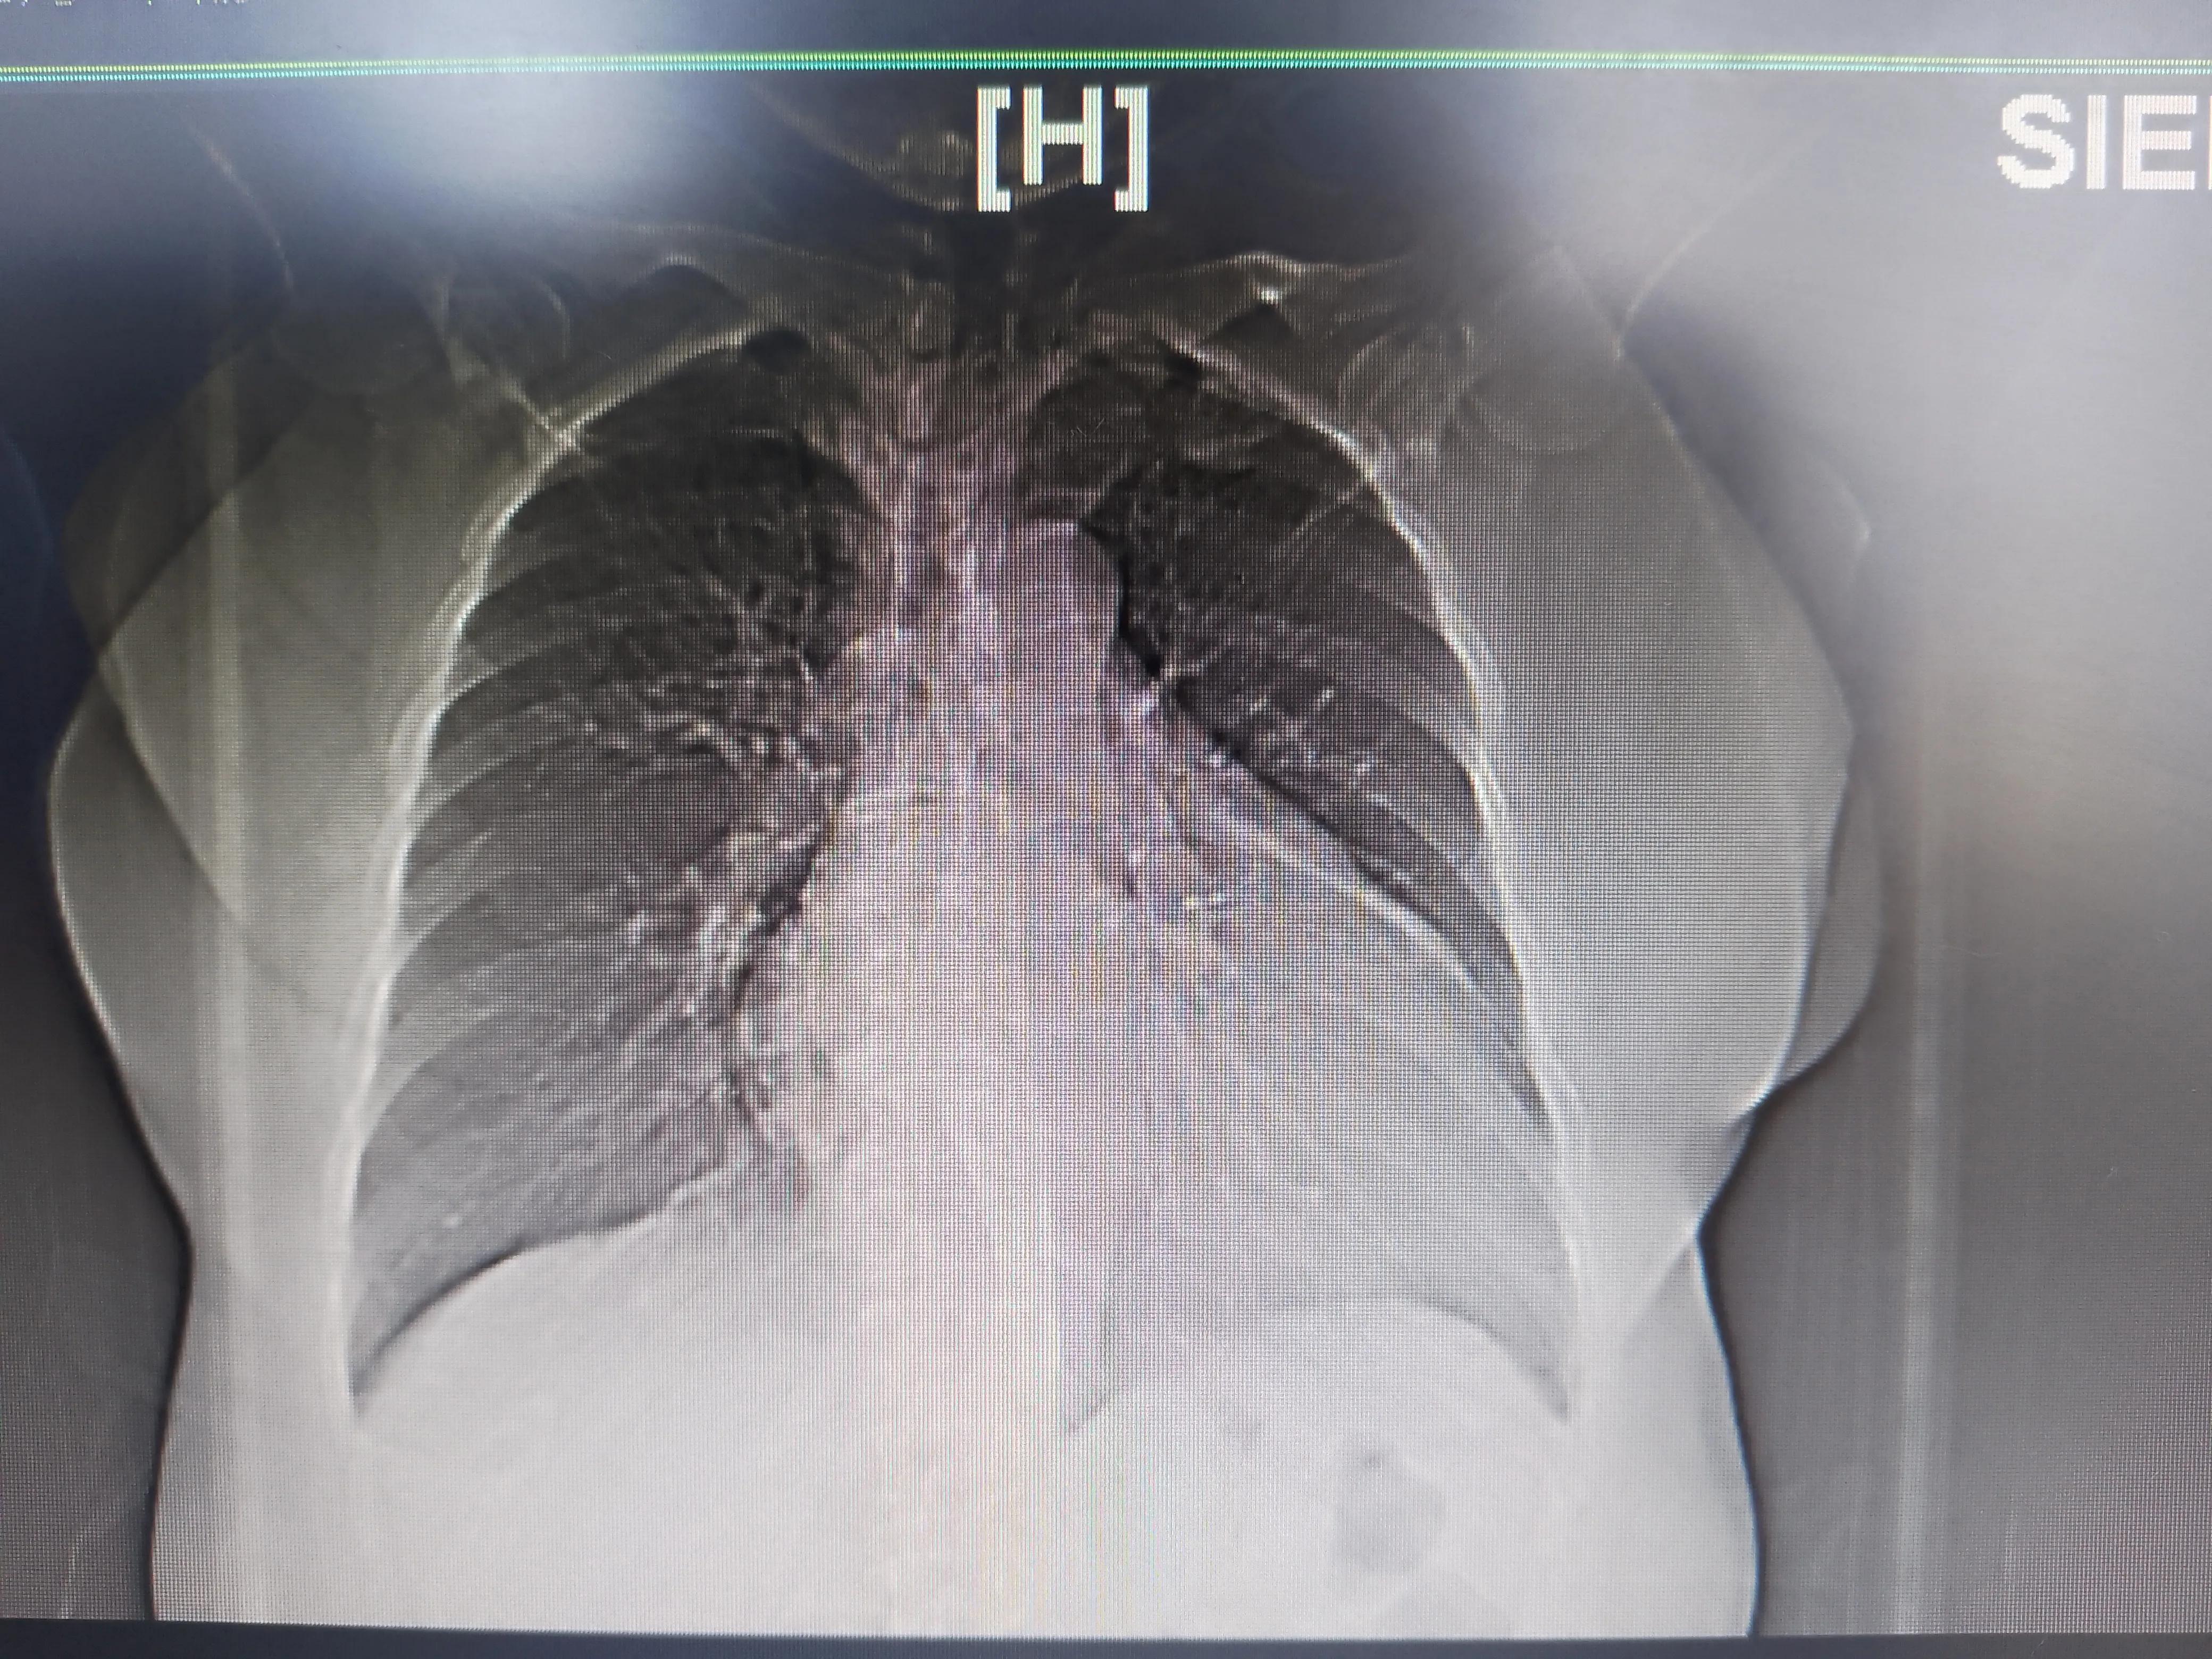

同时肺静脉CT里面发现肺里很干净,没有结节也没有明显的急性或慢性炎症;右心明显扩大导致心尖上翘。

右心明显扩大

右心明显扩大,肺挺干净的